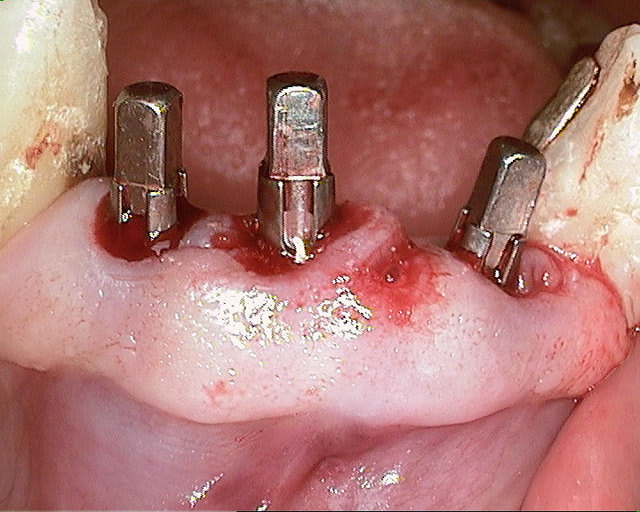

un cas récent os vestibulaire très fin.